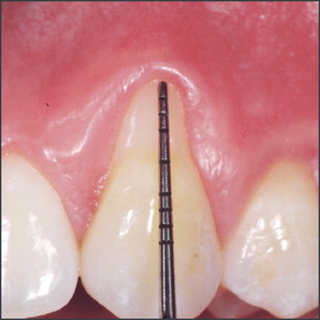

Before treatment with Straumann® Emdogain®.

Courtesy of Prof. Giovanni Zucchelli

8 months after treatment with Straumann® Emdogain®.